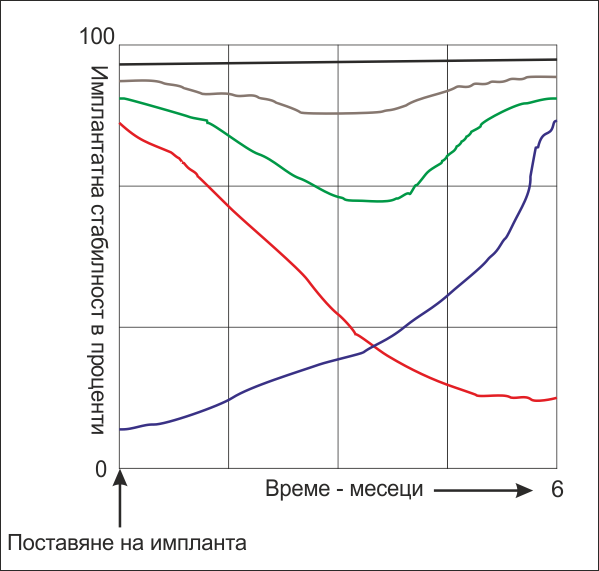

Какво се случва в костта при поставяне на

зъбни

импланти? Това е една графична схема на процесите, които се наблюдават в

костта за период от няколко месеца. При зъбните импланти се говори за

първична и вторична стабилност - първичната се определя от механични фактори

(дизайнът на импланта), а вторичната - основно от биологични фактори

(имплантатната повърхност, заздравителните процеси в костта, обмяната и

храненето на периимплантатната кост и меките тъкани и много други). Все пак

дори и тези принципи не са валидни на 100 % - дизайнът на импланта има

значение за вторичната стабилност, а качеството на костта и имплантатната

повърхност също играят роля за първичната стабилност на импланта. Първична е

стабилността през първите няколко месеца, а вторична - след приключването на

остеоинтеграцията. На горната схема с червена линия е означена

първичната стабилност, а със синя - вторичната. И двата типа стабилност се

измерват в проценти, като за измерване се използва апаратът

Ostell, който излъчва ултразвукови вълни и измерва

доколко имплантатът е срастнал с костта. При 100 % измерена стойност има

пълна

остеоинтеграция, а при 0 % - пълен провал в лечението. Характерно за

първичната стабилност е намаляването на стойността с течение на времето -

поради компресия на костта, влошено хранене, прогресираща костна резорбция и

т.н. фактори. Обратно, с течение на времето вторичната стабилност нараства -

поради синтез на нова костна тъкан, минерализация и добре протичащи

оздравителни процеси. Сумарната имплантатна стабилност е означена със зелена

линия на горната графика - тя е резултат от наслагването на линията на

първичната и вторичната стабилност. Вижда се едно хлътване през периода от

четвъртата до шестата седмица - това е т.нар. критичен период, през който

има опасност от провал в имплантатното лечение и не е добре да се натоварва

имплантатът - или се натоварва рано, или отсрочено, през четвърти - шести

месец. Повечето автори са единодушни че около шестия месец остеоинтеграцията

вече е приключила. Повечето

съвременни имплантатни системи се стремят към

идеалния случай - черната линия, при който критичен период липсва и

имплантатната стабилност е постоянна, близо до 100 %. Все пак от медицинска

гледна точка стойности от порядъка на сто процента се постигат изключително

рядко - в идеалния случай, добрите имплантатни системи би следвало да

следват линията, означена с кафяво на горната графика - хлътването е съвсем

минимално. Такъв клиничен резултат е напълно постижим - чрез подобряване на

формата на импланта и неговата повърхност, което е резултат на доста

проучвания и непрекъснато усъвършенстване на зъбните импланти. Така например

при много съвременни имплантатни ситеми се говори за концепцията

any time loading - натоварване по всяко време без

да се съобразяваме с критичния период. В действителност, при

класическото имедиатно натоварване до 48 часа след поставяне на импланта

зелената крива губи своето значение - преди хлътването имплантатът вече е

натоварен и, както стана въпрос по-горе, остеогенезата се стимулира.

Критичният период при тези условия няма да се усети по никакъв начин. Дори

според доста автори при по-голям по размер имплант няма нужда и от шиниране

на изработената корона; при имплантатен блок пък сигурността е още